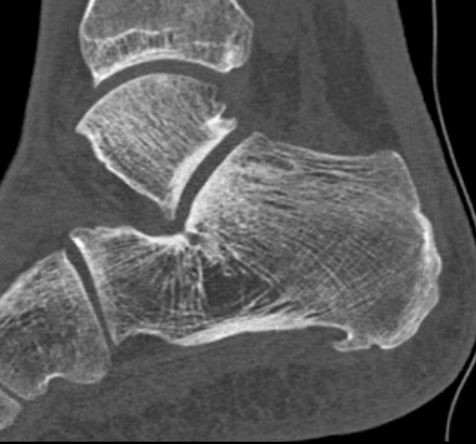

Abb. 9a–d: chron. Plantarfasziitis mit plantarem Fersensporn und Irritation Baxternerv plantar lateral

Kasuistik: 28-jähriger Patient, Profisportler.

Abb. 9a: Plantarer Fersensporn und Plantarfasziitis im MRT prä-op.

Abb. 9b: Plantarer Fersensporn im CT prä-op.

Abb. 9c: Lateraler Zugangsweg bei atypisch weit nach plantar lateral liegendem Sporn.

Abb. 9d: Röntgenkontrolle nach Minioffenem Plantarfaszienrelease und Abtragung Fersensporn mit Neurolyse.

Zum Lesen der Bildbeschreibung und zur Vollansicht bitte die Bilder anklicken. Bilder: Manfred Thomas.